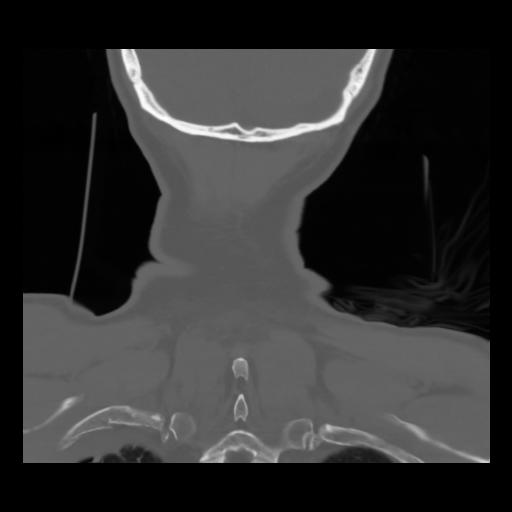

13 P.BLANDAS,,Coronal,2.000,P.BLANDAS,Coronal,